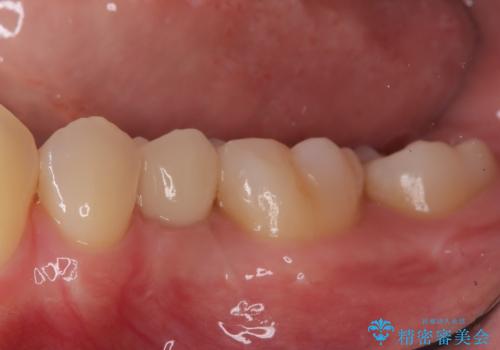

小臼歯のインプラント

- 小臼歯が先天性欠損していたため、インプラントにて補綴しています。